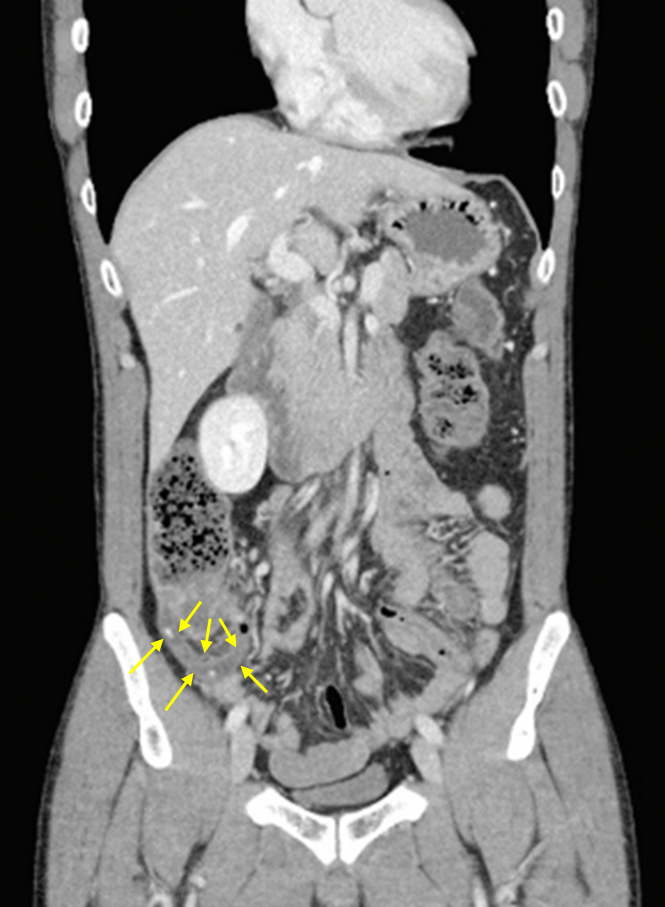

43세 남자가 하루 전부터 배가 아파서 병원에 왔다. 하루 전에 과식한 뒤 오른쪽 아랫배가 아프고 구역감이 생겼다. 혈압 125/85 mmHg, 맥박 83회/분, 호흡 21회/분, 체온 37.4℃ 이다. 오른쪽 아랫배에 압통과 반동압통이 있다. 혈액검사 결과는 다음과 같다. 복부 컴퓨터단층촬영 사진이다. 치료는?

Img | CT: 막창자꼬리염 소견 |

• 위 환자는 급격히 시작된 복통과 오른쪽 아랫배에 특징적인 압통과 반동압통 증상, CT 상 충수돌기염 소견으로 봤을 때 쉽게 진단이 가능하다.

진단 | • 복부 CT: 충수돌기 distension, wall thickening • 초음파: 충수돌기 지름 > 7mm |